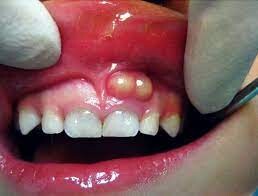

A tooth abscess is a bacterial infection found in the inner part of the tooth where pus has collected and can cause moderate to severe pain in people who suffer from the condition. Tooth abscesses can occur when a cavity has gone untreated for too long or when a crack or chip in the tooth allows bacteria to find its way into the dental pulp (the inner, soft part of the tooth) area of the tooth and gets infected.

Once the bacteria has made its way inside, it will spread down to the root and cause both inflammation and swelling. Once inflammation occurs, it will force the pus into a tight space (known as the abscess) at the tip of the root where the swelling exists.

If you experience any of the signs or symptoms listed above, you should see your dentist immediately, especially if you begin to experience swelling in your face or begin to feel feverish. If your dentist cannot see you immediately, you should go to an emergency room as it’s possible these symptoms indicate the infection is possibly spreading into your jaw and the surrounding tissue.

The only way to rid yourself of both the pain and the condition is to get proper dental treatment. You may feel a lessening of pain if the abscess ruptures, but you’ll still need to get a professional’s help. The infection could spread to other parts of your jaw and beyond to parts of your head and neck and, in a worst-case scenario, lead to sepsis, which is an infection throughout the entire body that can put your life at risk.

Tooth Abscess Treatments

Treating a tooth abscess involves draining the abscess and ridding the area of the infection. The tooth itself may be saved with a root canal treatment, but in some instances, it may need to be removed completely. Leaving a tooth abscess untreated can lead to serious, even life-threatening, complications. Your dentist or oral surgeon may recommend the following:

Root Canal Procedure — If possible, your dentist will try to save your tooth by performing a root canal. The tooth is cleaned and disinfected on the outside, drilled into and cleaned out from the inside and then filled with a safe adhesive cement to restore structural integrity (and protect the tooth from future infection). If taken care of, this restored tooth will last your entire lifetime.

Extract or Pull the Affected Tooth — Extracting the tooth is a last resort, but if the tooth cannot be saved, your dentist will elect to choose this option to preserve the health of the rest of your mouth. Once extracted, the abscess will be fully drained and cleaned to prevent further infection.

Antibiotics — If the infection is localized around the abscessed area, you may not need antibiotics. However, if the infection has spread beyond it, your dentist will prescribe antibiotics to help slow or diminish the infection, especially if you have a weakened immune system.

While the area is healing, your dentist may recommend that you regularly rinse your mouth with warm salt water and take over-the-counter pain relievers as needed to help ease any discomfort you may encounter.